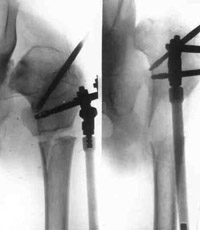

Schanz-Ilisarov's operation with elongation of hip.Schanz-Ilisarov's operation with elongation of hip.

Schanz-Ilisarov's operation with elongation of hip.

Schanz-Ilisarov's operation with elongation of hip.Dismantling of Ilisarov's apparatus.